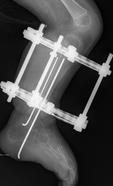

先天性胫骨假关节

肢体短缩延长术,延长9厘米

术前 手术 术后功能恢复良好